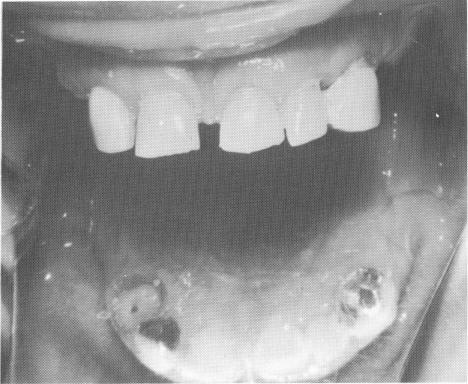

Fig. 15-99. A maxillary arch with six loose teeth and a large anterior diastema.

In this case there are six anterior periodontally involved teeth, including only a root of the right

cuspid, and a large diastema between both central incisors (Fig. 15-99) . The teeth were prepared, and

castings made with palatal extensions emanating from the lingual shoulders of the central incisor copings.

The copings were not over-built to close the diastema.